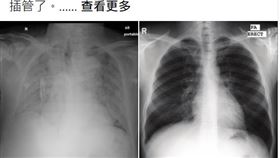

染疫肺整片白 醫:病患24小時內亡

國內疫情嚴峻,染疫個案漸增,23日,中央流行疫情指揮...